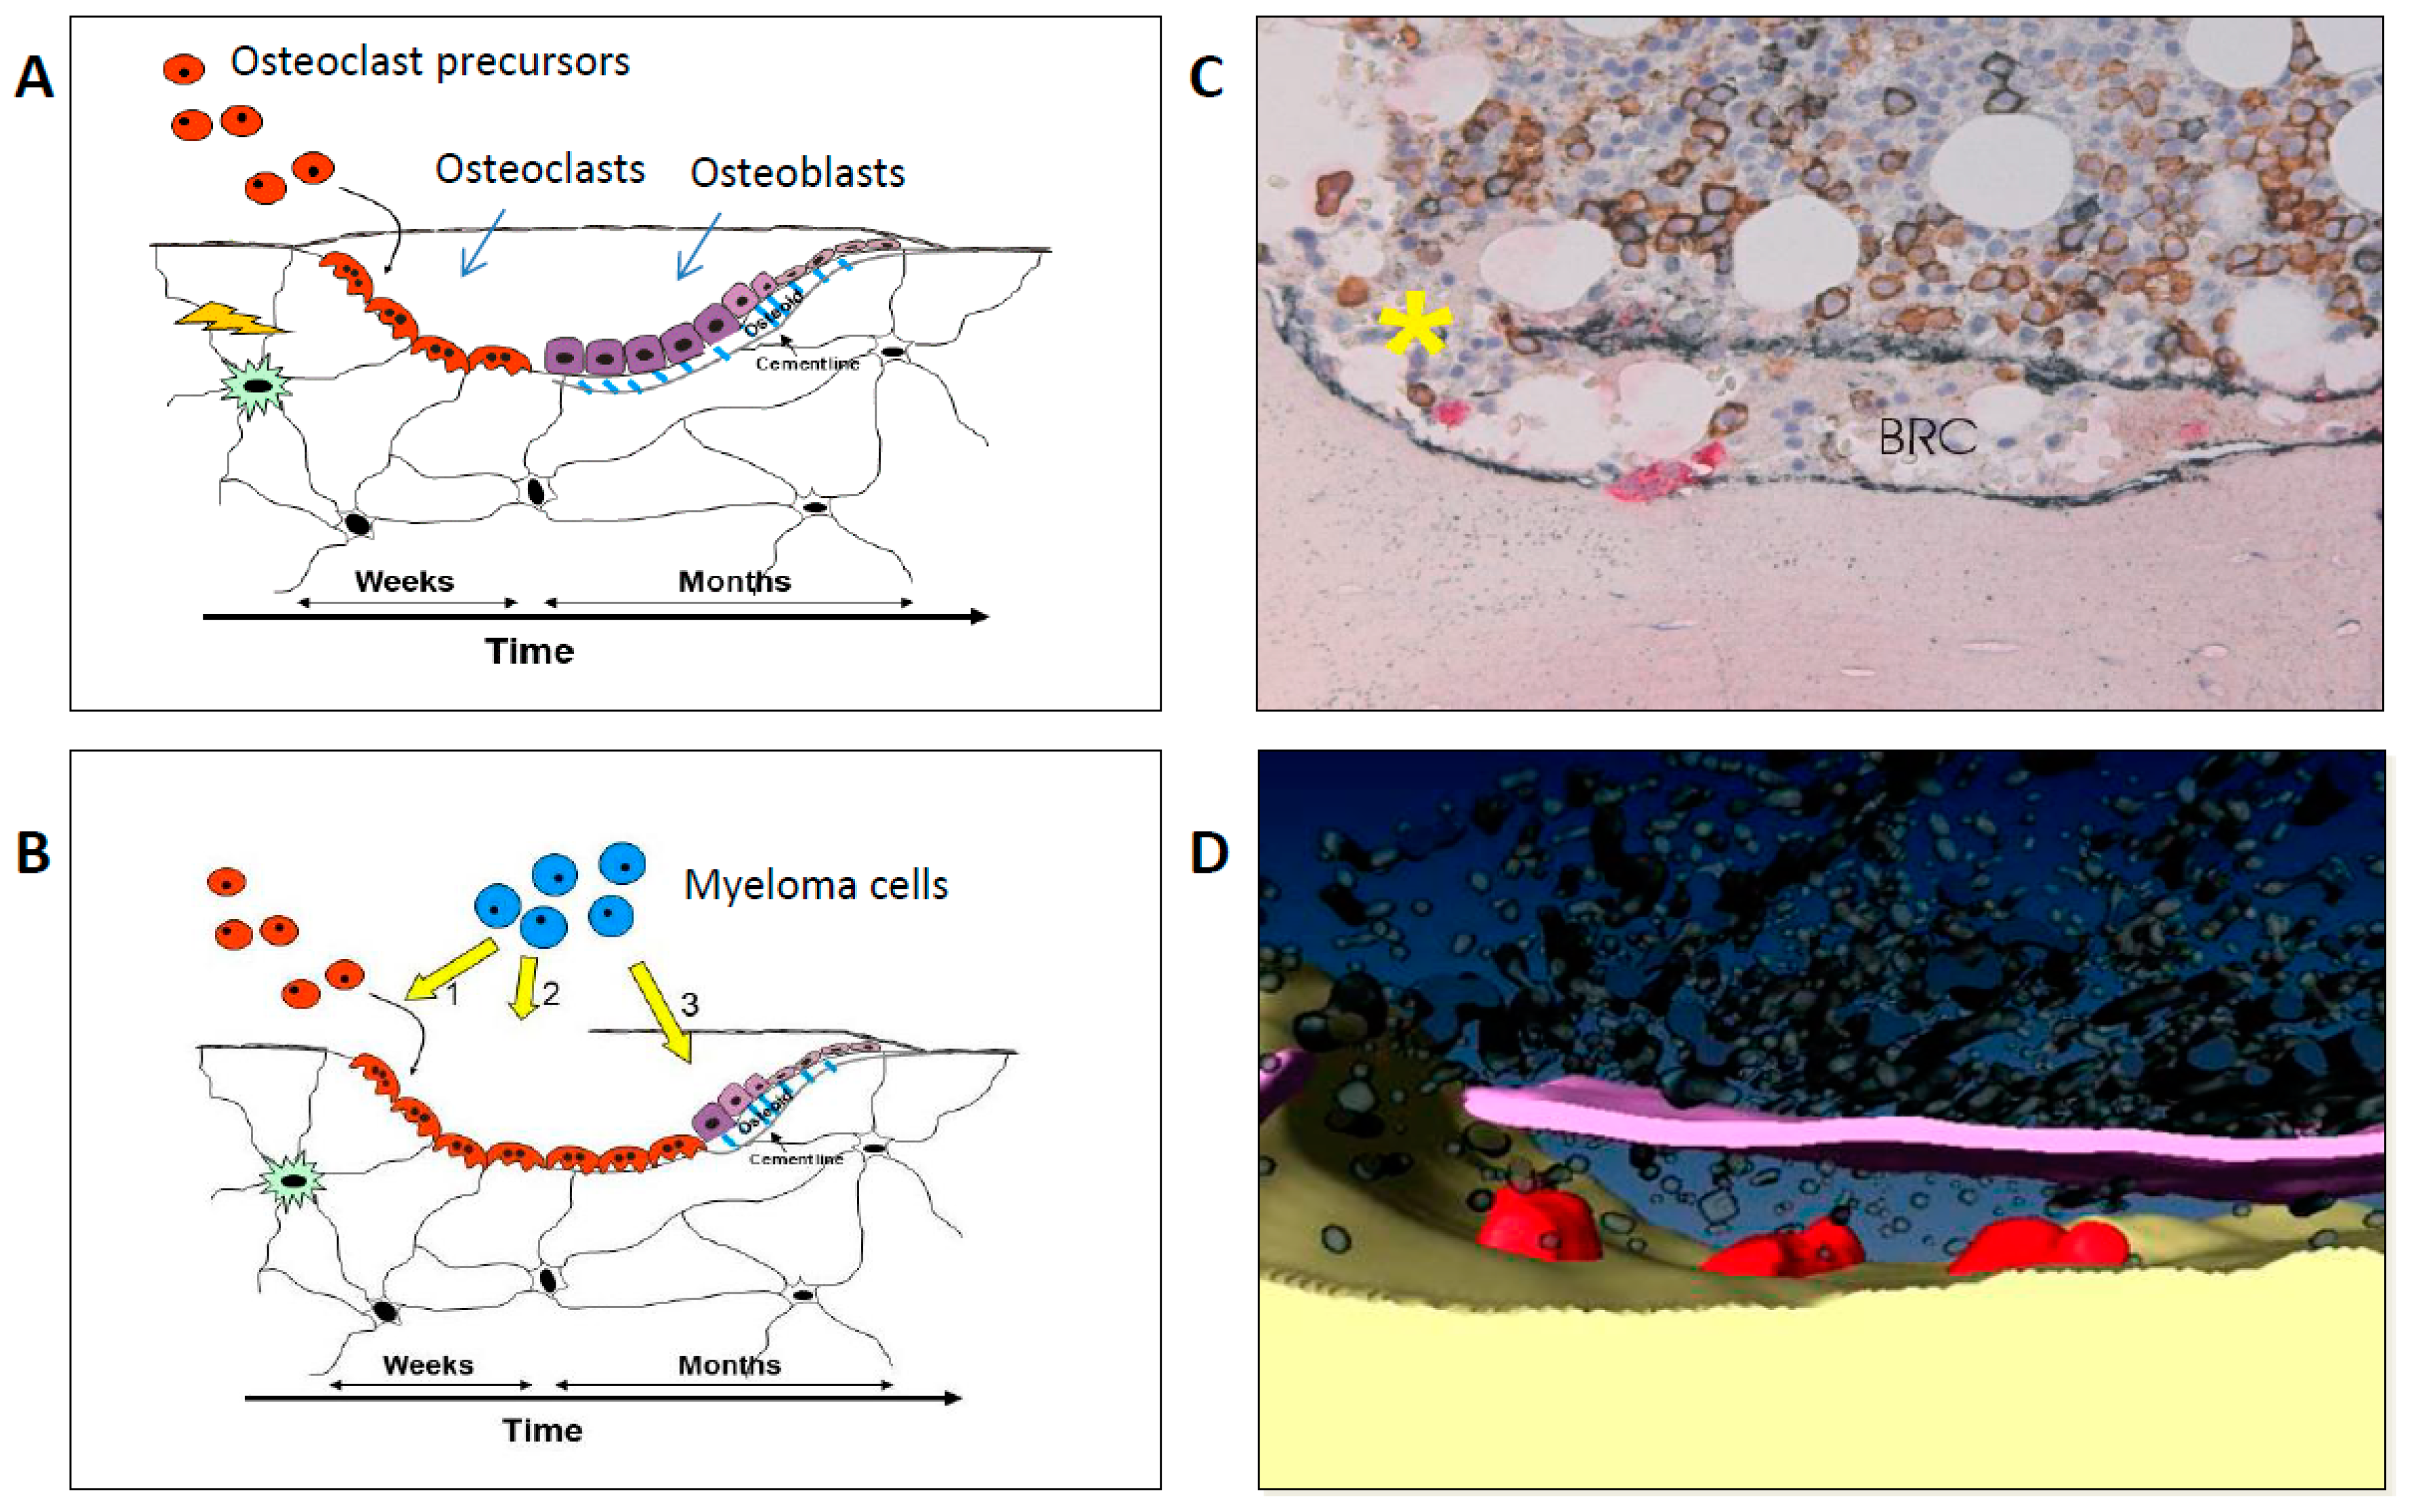

2. Pathophysiology